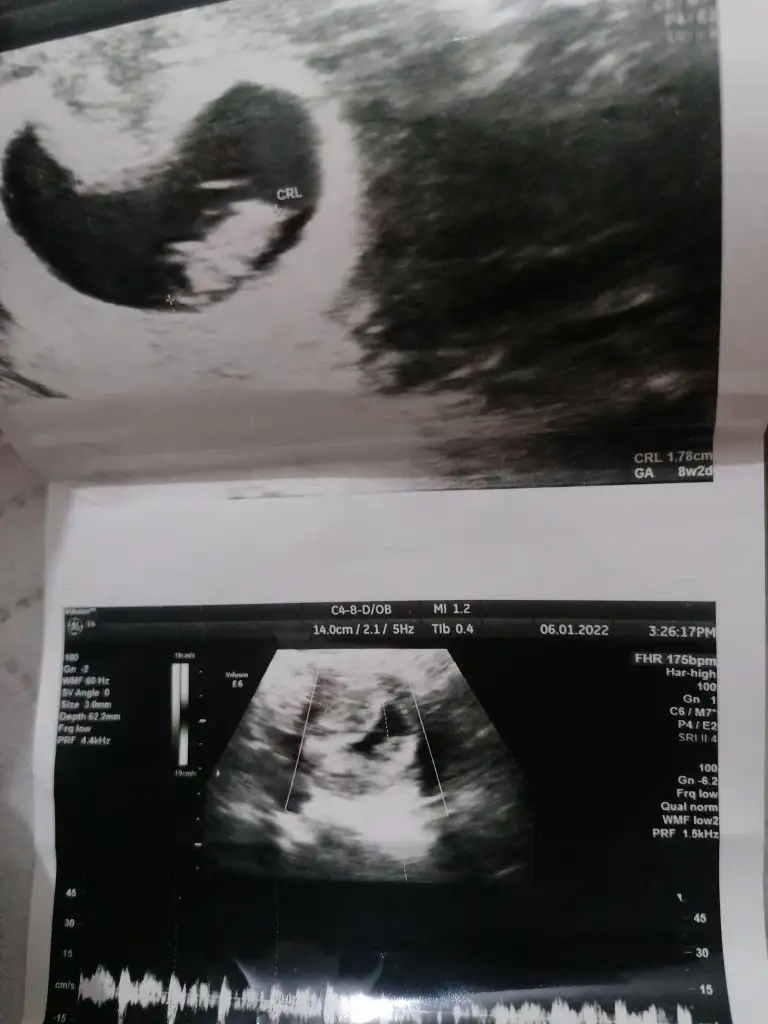

Benide tahmin efermisiniz

Henüz çok küçük biliyorum 11 haftalık olduk tahmin alabilirmiyim... Ikra meyra Ikra meyra

12+6 yorumlarmısınız lütfenn🌸🌸🌸Şimdiden teşekkürler 🙏

Merhaba benimde ikizlerime bakar mısınız😌 biri 11+4 biri 11+2günlük resimde 😍